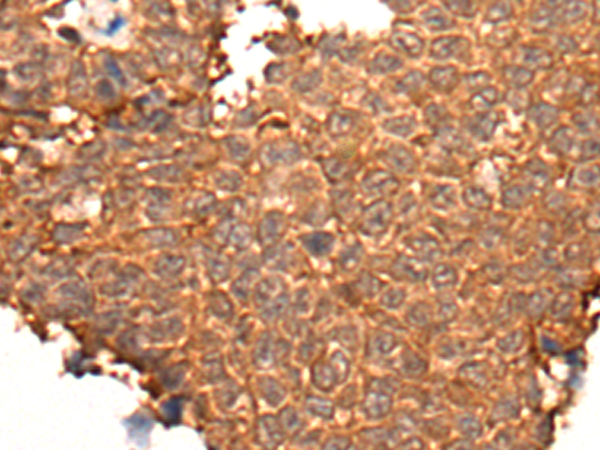

IHC positive control: |

Human ovarian cancer and human gastric cancer |